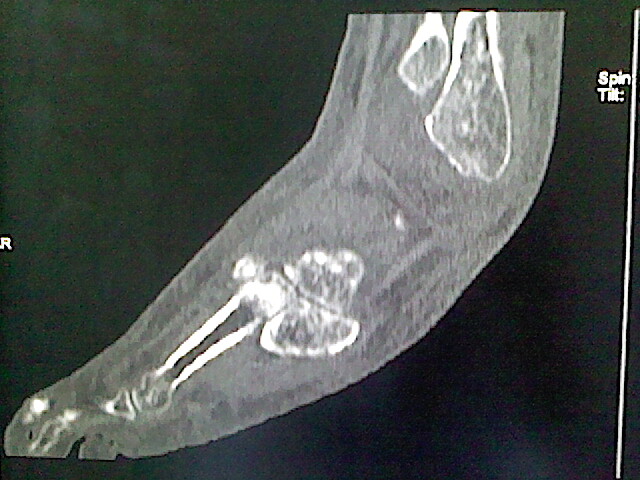

男,76岁,左小腿疼痛,不能站立

本例骨质改变主要表现为滑膜或韧带区的骨侵蚀融解(胫腓联合区骨质破坏无硬化边),距骨后部骨质破坏区有硬化边及死骨样改变.所以,本例考虑关节结核可能性大,绒毛膜结节性滑膜炎多发于中年,且极少见于膝髋以外的关节,骨质硬坏也以压陷吸收为主,有明显的硬化边,骨膜增生呈结节状(可以mr鉴别),所以本例暂除外.

另不除外可引起相似表现的其他炎症如布氏杆菌性关节炎等